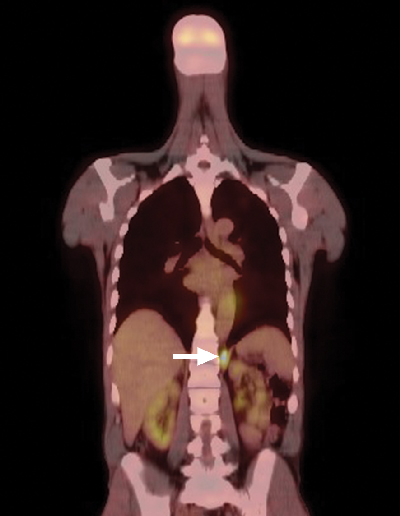

A positron emission tomography scan showed mildly increased fludeoxyglucose activity at the right thyroid bed, consistent with low-volume residual disease, and intense activity in the left retrocrural soft tissue (Box 2). Biopsy specimens were obtained from both sites and were found to be histologically consistent with parathyroid cancer. The patient underwent a planned resection of the known sites of disease, beginning with a right-sided neck dissection. Thereafter, he underwent a left thoracotomy, which showed more extensive pleural deposits and bulky metastatic disease over the diaphragm and crura, only amenable to debulking. A left pleural effusion, non-malignant on cytology, complicated his postoperative recovery.